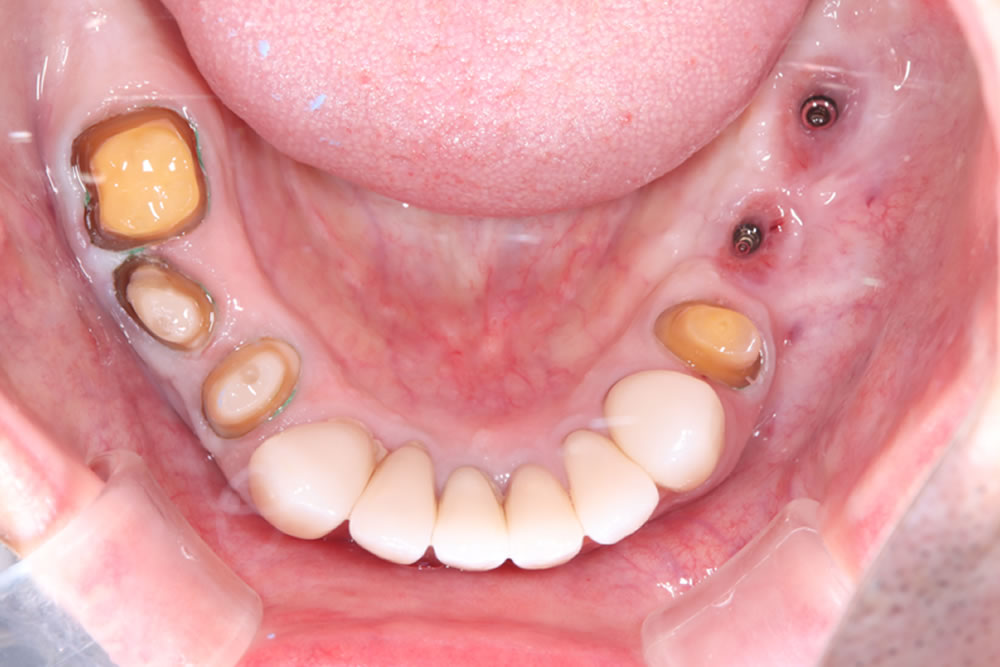

インプラント結合後に全顎精密仮歯の装着

インプラント手術から3ヵ月後、上下顎プロビジョナルレストレーション(仮歯)を装着しました。

- 上顎は総義歯

- 下顎左5・6番はインプラント

- 下顎その他はクラウン